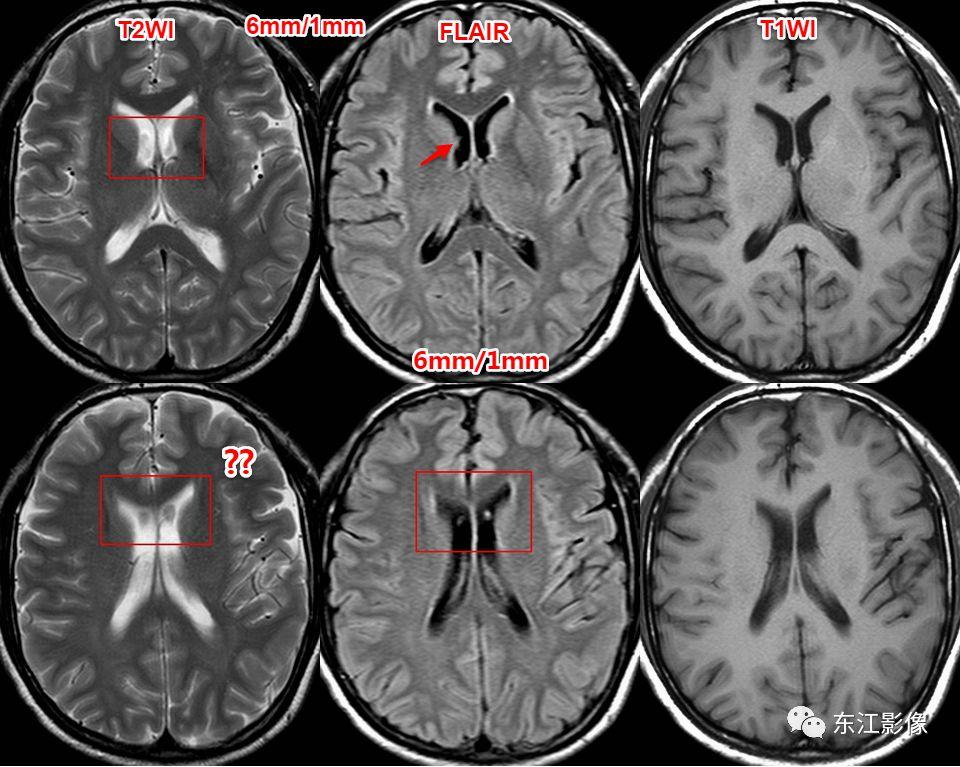

5. 脑脊液流动伪影

- 脑脊液流动伪影主要见于T2WI、FLAIR,主要是长TE序列容易出现流空效应的缘故。

- 但由于脑脊液流动方向、速率不一等因素的影响,呈现为非脑脊液信号影像,部分呈囊样。

- 常见于第三脑室、侧脑室室间孔旁区、脑干周围脑池(这些区域结构复杂)。

- 鉴别要点,T1WI、增强未能辨认;DWI与邻近一致的无信号;无占位效应。

侧脑室室间孔旁脑脊液流动伪影。

又一例。